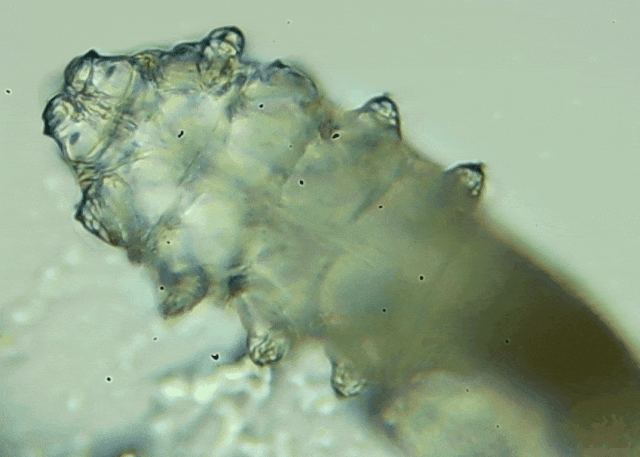

蠕形螨是一類肉眼看不見的寄生螨,常見的有毛囊蠕形螨和皮脂蠕形螨,常駐在人類的毛囊和皮脂腺里,尤其是眼睛的瞼板腺和睫毛根部。數(shù)量少時(shí),蠕形螨能與人體“和平共處”,但一旦你免疫力下降、油脂分泌旺盛或清潔不到位,他們就會(huì)以你難以想象的速度瘋狂繁殖。

而且這不是極端個(gè)案,廈門眼科中心干眼門診的臨床數(shù)據(jù)統(tǒng)計(jì),眼睛經(jīng)常紅癢發(fā)炎的人群,多數(shù)都有螨蟲,約80%以上的瞼緣炎患者螨蟲超標(biāo),一根睫毛最多能有幾十只。

高發(fā)的2類眼部健康危【文章導(dǎo)讀】我只是眼睛癢,結(jié)果醫(yī)生說我睫毛里有80只蟲?這不是恐怖片,而是真實(shí)的病例:武漢一13歲男孩,右眼9根睫毛里檢出39只螨蟲,左眼9根里檢出47只。 而且這不是極端個(gè)案,廈門眼科中